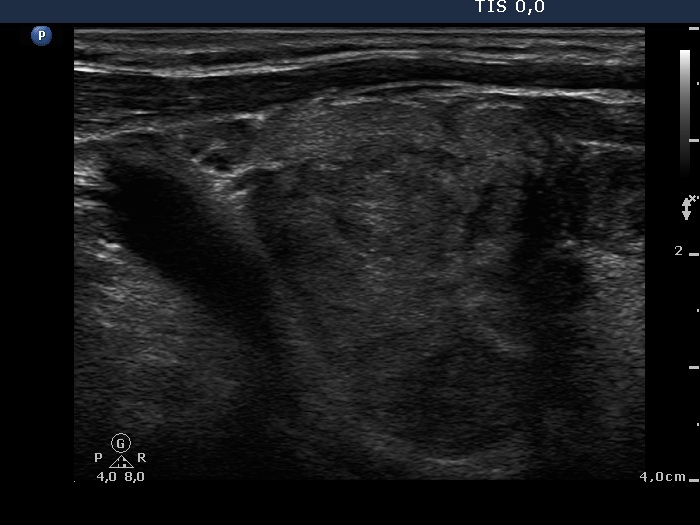

Right lobe, longitudinal scan

Left lobe, longitudinal view. The borders of the nodule are irregular, lobulated and the nodule presents longer-than-wide shape.